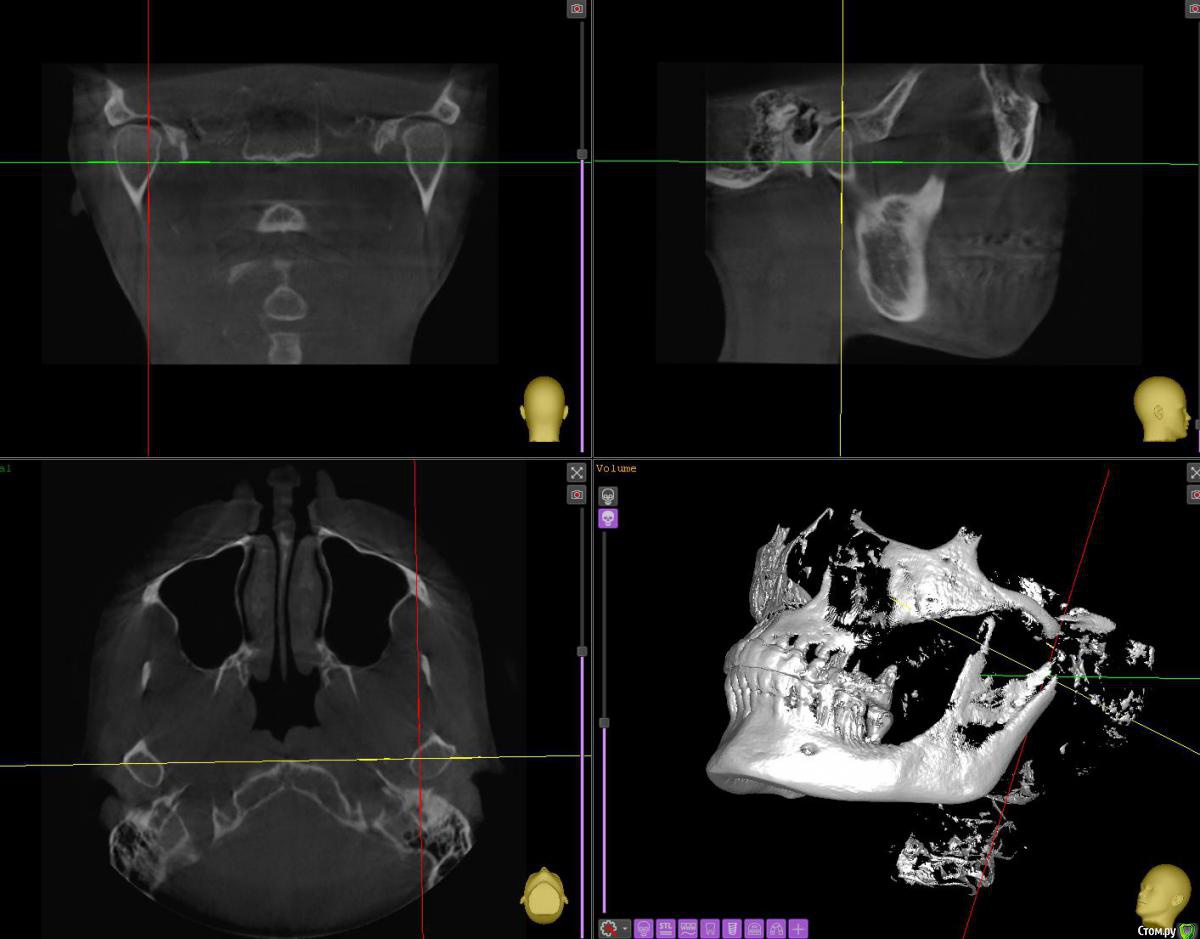

АнтонТЛТ Опубликовано 29 июня, 2020 Поделиться Опубликовано 29 июня, 2020 Срезы надо иначе выставлять, крутануть перекрестие. Примерно чтобы вот так получилось. Ссылка на комментарий

АнтонТЛТ Опубликовано 29 июня, 2020 Поделиться Опубликовано 29 июня, 2020 Вот так короче) 1 Ссылка на комментарий